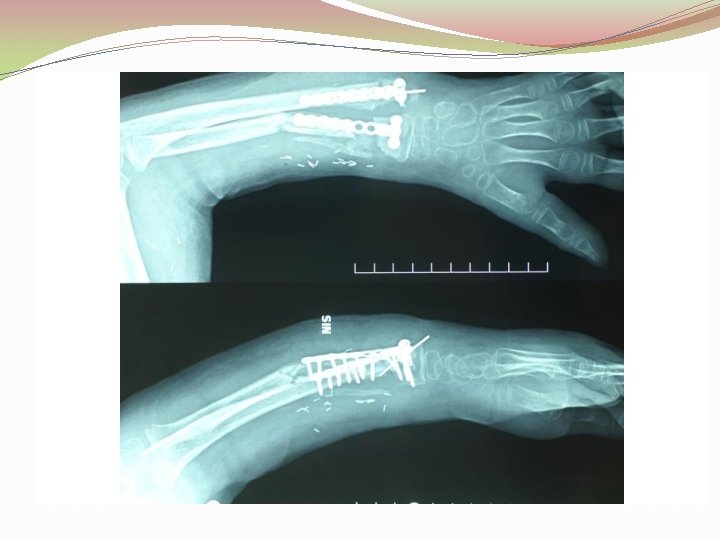

Ķirurģiska ārstēšana Osteomielīta pacientiem jāveic radikāls debridement ķirurģiski, kas ietver visu procesā iesaistīto audu rezekciju: �Mīksto audu rētas rezekcija �Cīpslu kalcinātu rezekcija �Distantu sekvestru rezekcija �Kaula rezekcija līdz vizuāli veseliem audiem – readzama punktveida asiņošana ´Paprika sign’. Bogdan Maciuceanu, Lucian Jiga, Alexandru Nistor, Jenel Marian Pastrascu, Mihail Ionac Chronic Osteomyelitis of Long Bones Timisoaral Medical Jornal, 2005

Ķirurģiska ārstēšana Veiksmīgas ķirurģiskas ārstēšanas stūrakmens ir mirušas telpas ‘Dead space’ aizpildīšana, kas izveidojas pēc debridemet veikšanas Brad Parsons, Elton Strauss, Surgical management of chronic osteomyelitis, The American Journal of Surgery 188 (Suppl to July 2004) 57 S– 66 S

Debridement Os konstrukciju evakuācija Biopsija un mikrobioloģija Dobuma slēgšana Antibakteriāla terapija Stabilizācija (Ārējā fiksācijas aparāts) Maina vai apstiprina antibakteriālo terapiju Mīksto audu rekonstrukcija 6 nedēļas antibakteriāla terapija (pēc debridement) Pseidartroze Konsolidācija Atkārtot ārstēšanu Luca Lazzarini, Jan T. Mader, Joson H. Calhaun Osteomielitis in Long Bone, The journal of bone&joint surgery, Volume 86 A, nr 10, 2004